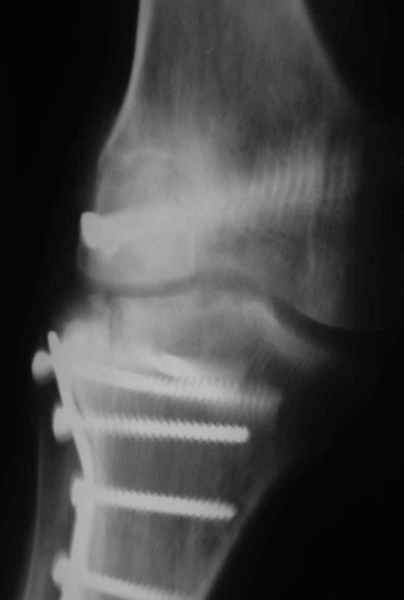

Как вариант решения прогрессирующей вальгусной деформации коленного сустава я бы предложил косую остеотомию дистального отдела бедра с фиксацией пластиной и компрессирующим винтом.

Взгляните на снимки , может быть это вам поможет.

Около 5 лет применяю этот тип дистальной остеотомии бедра для коррекции механической оси Н/К ( более 20 случаев) - достаточно эффективная операция.

- Конечно, другая: я применял этот тип остеотомии при различных состояниях, приводящих к деформации механической оси сустава, но техника её тандартна,

расчеты индивидуальные.

-Деформация оси сустава может быть варусной или вальгусной, причины - структурные изменения в латеральном -или медиальном отделе сустава (переломы, патология зон роста, дисплазии, дегенеративные процессы) результат лечения внутри- или внесуставного перелома и восстановление оси обуславливается анатомичностью репозиции и адекватностью фиксации. Нередко в запущенных -неправильно срасшихся unicompartmental внутрисуставных переломах восстановление оси и опороспособности достигается периартикулярными

остеотомиями...